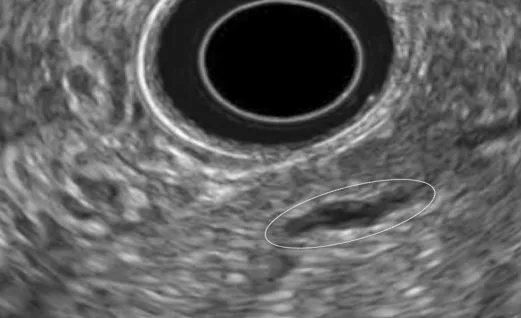

Figure 13. Aspect échoendoscopique de la PAI de type II. Noter l’épaississement hypoéchogène de la paroi du CPP responsable d’un aspect filiforme de la lumière du CPP